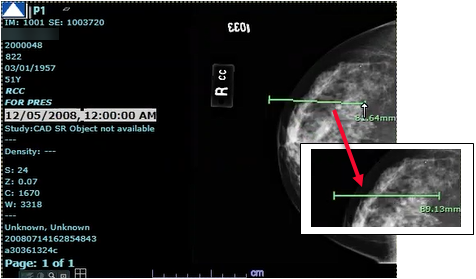

Synapse offre plusieurs options pour les annotations d’image : angle, règle, RCT, texte et RI (région d’intérêt). Une image peut comporter plusieurs annotations ; vous pouvez accéder aux options d’annotation à partir du menu contextuel.

La précision des mesures dépend de la précision des informations provenant de la modalité. La fonctionnalité de mesure calcule la longueur de ligne, l’angle, la surface, le périmètre et d’autres statistiques à l’aide des informations fournies par la modalité. Sa précision repose donc sur la modalité d’imagerie d’origine.